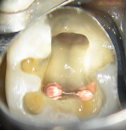

Conventional Treatment with Standard Core Restoration

Non-surgical endodontic treatment with resin core build up